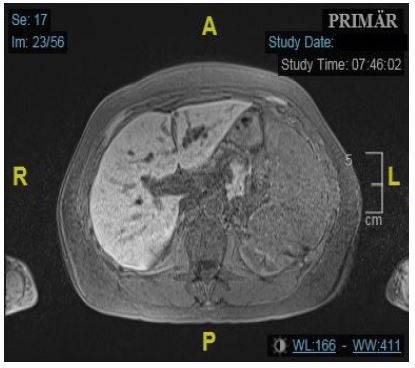

Ten years prior, she had been hospitalized with an inflammatory myopathy diagnosed as a polymyositis, likely related to SjS. To rule out a neoplastic aetiology, a magnetic resonance imaging (MRI) of the abdomen was performed. The MRI coincidentally revealed a 20 mm stricture of the left bile duct with a poststenotic dilatation and multiple small cysts in the vicinity (Figure 1). The right bile duct and the common hepatic duct were not involved. The stricture was suspicious to be caused by a hilar cholangiocellular carcinoma, also termed as Klatskin tumor. An Endoscopic Retrograde Cholangiopancreatography (ERCP) including papillotomy confirmed the segmental stricture and poststenotic dilatation of the left bile duct, suggesting malignancy, but brush cytology showed no carcinoma. Unfortunately, the patient developed an iatrogenic duodenal perforation and an infected retroperitoneal hematoma as complications from the ERCP. She was treated with antibiotics, recovered well, and the hematoma resolved over the following months.

Figure 1: Axial T1w-fs MRI: First observati on of stenotic left bile duct and additional cystic formations.